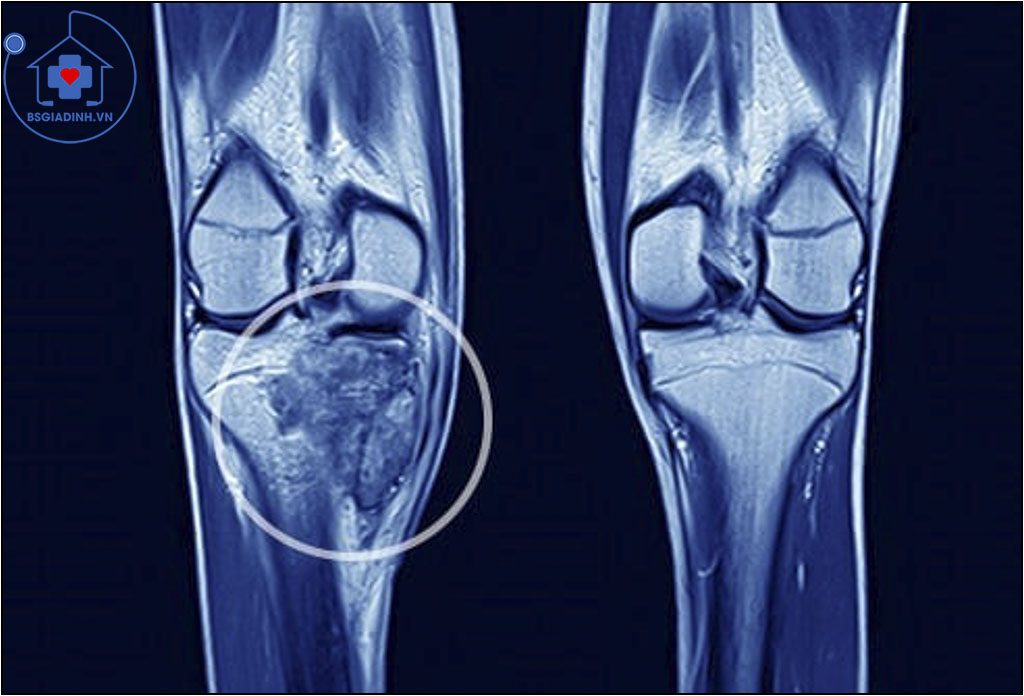

MRI (Hình ảnh cộng hưởng từ) cũng cho biết chi tiết những hình ảnh cắt ngang. MRI sử dụng từ trường rất mạnh liên kết với máy vi tính.